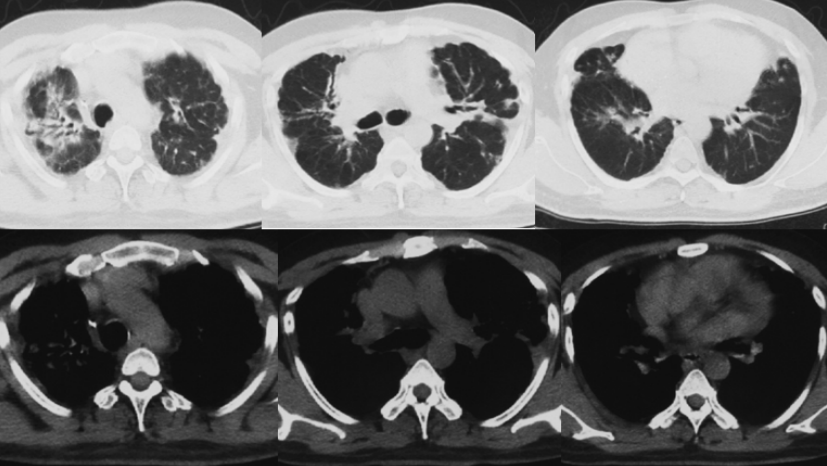

第4次住院(2021年10月24日-11月17日):2021年10月9日(停用激素后8个月)患者因“受凉”后咳喘加重,平地步行20 m即喘息明显,伴发热,体温最高38.5℃,痰中带血丝,约数口。当地诊所给予地塞米松(5 mg qd)治疗15 d,无明显改善,入当地县医院ICU住院,入院时测SpO2(未吸氧)60%。10月26日胸部CT:双肺弥漫磨玻璃影,散在斑片影,部分融合呈实变,双上肺胸膜增厚,较前明显加重(图7)。患者血气分析提示Ⅱ型呼吸衰竭,低氧血症明显,伴二氧化碳潴留,WBC和NEU升高,经治疗有所下降;生化指标可见LDH水平升高(表1~表3)。

诊断“间质性肺炎,慢阻肺急性加重期,支气管扩张,Ⅱ型呼吸衰竭”。抗感染20 d,激素治疗20 d(图9),鼻导管氧疗及NPPV。咳嗽、喘息明显减轻。胸部CT:对比10月26日,双肺斑片影、磨玻璃影明显吸收(图10)。11月17日评估病情好转出院,出院后继续口服甲泼尼龙12 mg qd(11月17-30日,13 d后自行停药)。

治疗调整(2021年12月4-19日):12月4日(停激素4 d)患者自觉喘息较前加重,再次就诊于当地市医院门诊,胸部增强CT:双肺斑片影较11月9日略吸收,双侧胸膜增厚如前(图11)。12月4日加用环磷酰胺50 mg qd至12月17日患者自行停用,并再次应用甲强龙24 mg qd,于12月18日减量至12 mg qd(图12)。

第5次住院(2021年12月20-24日):12月20日(甲强龙12 mg维持治疗中)受凉后再次出现咳喘加重,伴发热,体温38.0℃,伴肌肉、关节酸痛,流清涕,于当地市医院住院。血常规:WBC 11.46×109/L(↑),NEU 8.47×109/L,LYM 1.07×109/L,血红蛋白168 g/L,血小板327×109/L。血气分析(FiO2 0.41):pH 7.40,PaO2 115.5 mmHg,PaCO2 60.5 mmHg(↑),PFR 280 mmHg(↓),HCO3- 36.2 mmol/L。12月20日胸部CT:双肺新发散在淡薄渗出斑片影,部分结节影,较12月4日加重(图13)。予比阿培南、依替米星、莫西沙星抗感染治疗(图14),患者体温恢复正常,咳喘无改善,于12月24日转至我院。

2021年12月27日胸部CT:双肺弥漫网格影、斑片影及结节影,双侧胸膜增厚,双肺间质性肺炎可能,双侧胸膜增厚,双侧少许胸腔积液(图16)。